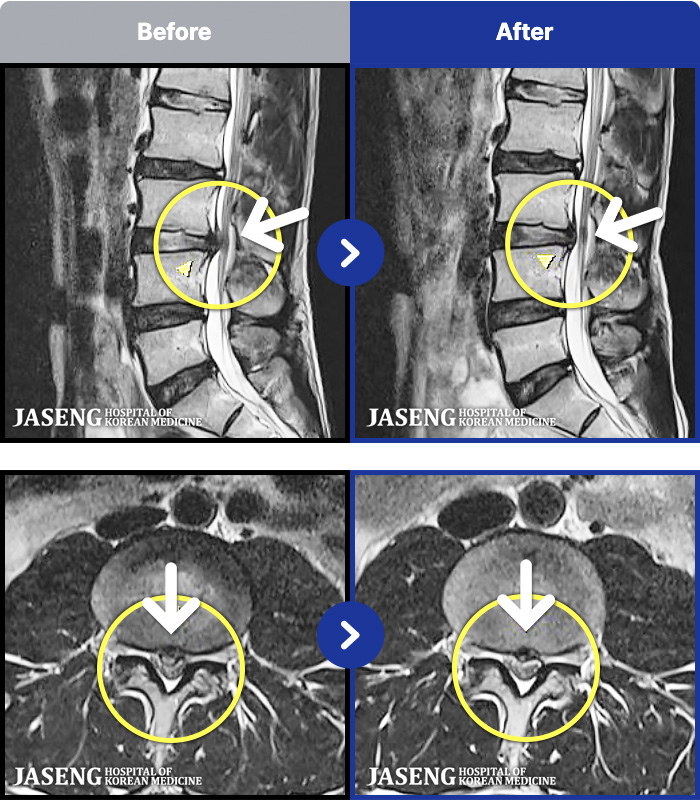

97 MRI ũ ʸ Ȯϼ.